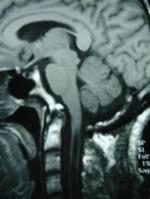

枕大池的有無、形態和大小變異在不同人都有變異,尤其是後兩者,變異較大。一般認為,可見於任何年齡, 報導率約千分之四。大枕大池更多地是個影像學名詞,因為大枕大池者一般第四腦室正常、無占位效應、無腦積水、無枕骨受壓變薄、後顱窩大小正常、無小腦蚓部萎縮等可能引起臨床症狀的因素。所以大枕大池的有與無、大與小一般認為臨床意義不大 。

有少數報導,枕大池增大者,有可能會有頭暈者、晃動時頭顱內有流水聲響的感覺,但這種感覺並沒有特異性,很難說真就是大枕大池引起。大枕大池如伴有小腦蚓部缺如和四腦室擴張,則形成所謂的Dandi2Worke綜合症。